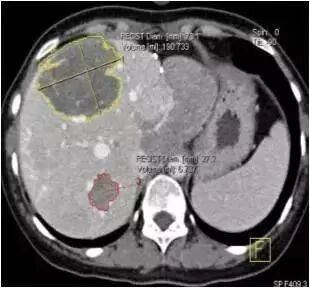

西门子双源CT(SOMATOM Drive)肿瘤分割技术可对肺、肝、淋巴结以及其它各部位组织病灶实施一键式自动分割 ,自动测量,并且提供多种重要的肿瘤学参数。为检查定性,手术、放化疗前后效果提供可靠依据。